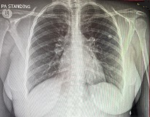

Diagnostic assessment: routine blood tests were done, the patient had normal electrolytes and renal functions with normal liver function tests, and lipase, but did, however, show a low Hb of 10.4 g/dL (normal range 12.0-15.0 g/dL). A plain chest radiograph showed no pneumoperitoneum, but significant hilar lymphadenopathy was seen in Figure 1. The abdominal ultrasound demonstrated a markedly tender spleen consisting of inhomogeneous echo texture with ill-defined areas of decreased echogenicity, and a round cystic component in relation to the hilum.

Figure 1: chest X-ray: demonstrating hilar lymphadenopathy (yellow arrow)